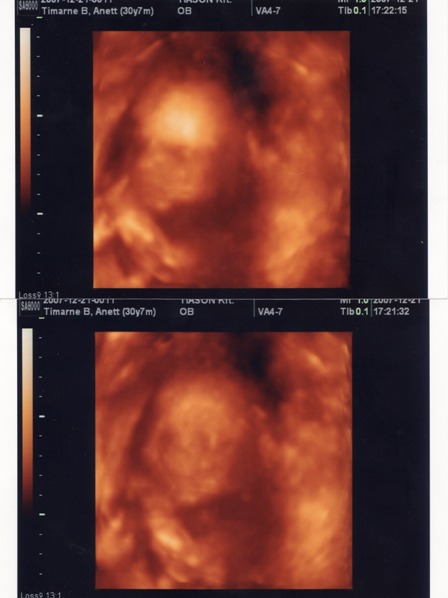

Képzeljétek, voltunk itthon 4D-s UH-n, és kisfiunk lesz